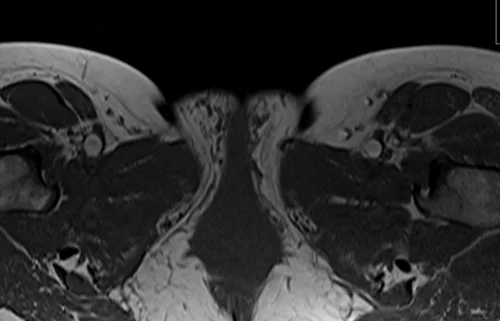

L plexus mri T1 axial images